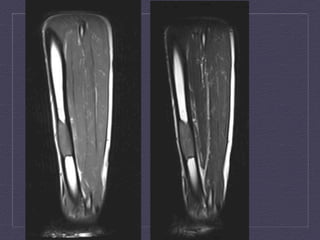

T1-­‐weighted,   T2-­‐weighted,   T1   fat-­‐satura:on   post-­‐contrast   MRI   studies  demonstrates  a  septated  mass  with  low  T1  signal,  increased   T2  signal,  and  rim  enhancement  within  the  intertrochanteric  region   of  the  right  femur